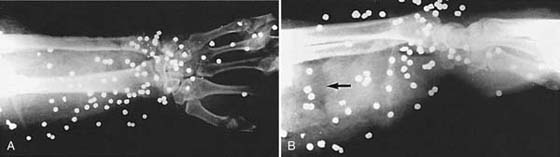

Figure 13-8 Posteroanterior (A) and lateral (B) views of the wrist and distal forearm showing multiple shotgun pellets. Note the air in the soft tissues (areas of lucency [arrow]) caused by the penetrating trauma.

Special Views